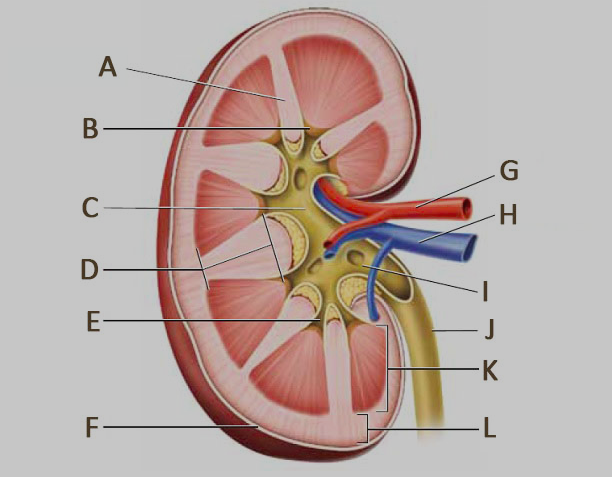

Calyx (of the kidney)

B & F

Medullary pyramids

G

A & B

D & E

Renal artery/vein

Renal capsule

Renal columns

Renal cortex

Renal medulla

I

Renal Pelvis

H

Ureter